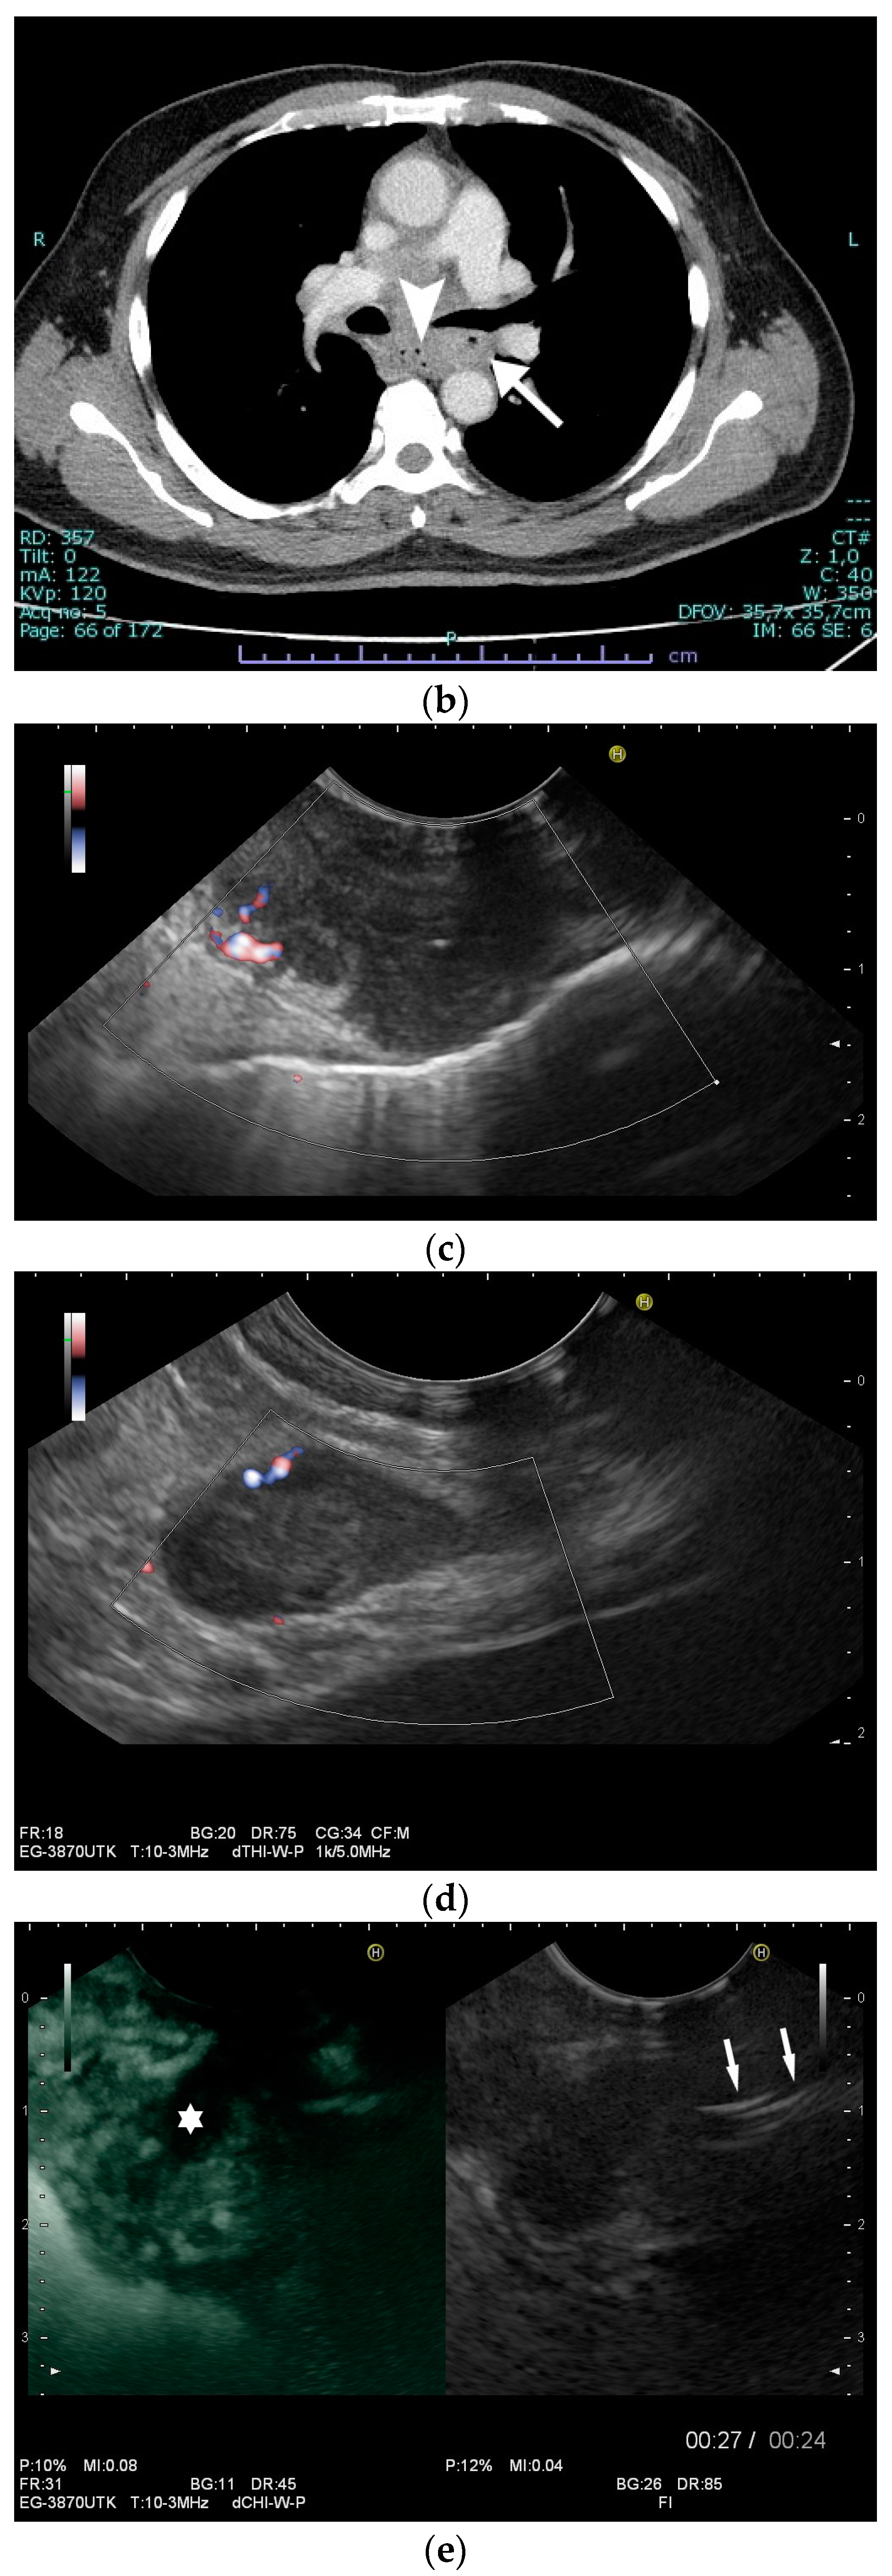

Esophagus: Esophageal tuberculosis accounts for <0.2% of all tuberculosis patients, and for only 2.8% of all gastrointestinal cases [89,93]. In 2022, two systematic reviews analyzed 133 and 311 cases of esophageal tuberculosis [94,95]. Esophageal tuberculosis is secondary to tuberculous mediastinal lymphadenopathy, which causes infiltration, ulcerations, bulging lesions, and narrowing of the esophageal wall [45,96]. Due to direct extending and spreading from infracarinal nodes, the middle third of the esophagus is usually affected [97,98]. Patients most often present dysphagia and retrosternal pain. Due to these symptoms and the accompanying weight loss, esophageal cancer is frequently suspected [99]. Complications of esophageal tuberculosis include bleeding, perforation, aspiration pneumonia, hematemesis, traction diverticula, esophageal strictures, and fistula formation [100]. In about 50% of cases, characteristic features of pulmonary involvement are detected during radiological imaging, and may help to establish the diagnosis [101]. Otherwise, the symptoms prompt esophagogastroduodenoscopy, with biopsy as the first diagnostic modality. Remarkably, esophageal tuberculosis can lead to variable endoscopic findings, ranging from esophageal ulcers or multiple nodules to a hypertrophic growth like an esophageal polyp, a subepithelial tumor, or tumor-like lesions [102]. Differential diagnosis should include sarcoidosis and Crohn’s (if an epithelioid granuloma without caseous necrosis is present), or carcinoma, lymphoma, and Behcet’s disease must be considered. Since caseating granulomas are usually located deep in the submucosal layer of the esophagus, endoscopic mucosal biopsies have a sensitivity of only 22%, with classical granulomas only being detected in half of the patients, and acid-fast bacilli only in one of four patients [102]. Endoscopic ultrasound most often visualizes infracarinal lymph node conglomerates with hypoechoic central lymph node areas [103] and hypoechoic homogeneous or heterogeneous lesions of the esophageal wall, with the possible interruption of the adventitia [45,96,104]. Fistula formation is possible [105]. Endoscopic ultrasound (EUS) and EUS-guided sampling play a pivotal role in confirming the diagnosis [103] [Figure 6a–i].

Figure 6.

A case of esophageal tuberculosis. A 52-year-old male non-smoker presented with progressive dysphagia and weight loss (15 kg in 6 months). Upper GI endoscopy revealed two subepithelial esophageal masses covered by normal mucosa (a). A CT scan showed large solid mass lesions in the mediastinum, with small gaseous inclusions (arrowhead) and a thickened esophageal wall (b, arrow). EUS ruled out a subepithelial esophageal tumor, and confirmed a large mediastinal hypoechoic mass infiltrating the esophageal wall, which was up to 12 mm thick with a complete loss of layering (c). Multiple enlarged and confluent hypoechoic lymph nodes were found throughout the mediastinum (d). Contrast-enhanced harmonic EUS showed the hyperenhancement of the mediastinal mass lesion and the thickened esophageal wall with some anechoic necrotic parts (*), and echogenic gaseous reflections (arrow; e). EUS-FNA (22 Gauge) of lymph nodes and of the thickened wall was performed (f; needle is marked with an arrowhead). Turbid fluid was aspirated from one lymph node, and then sent for cytological and microbiological examination and polymerase chain reaction (PCR) for mycobacteria. Positive Ziehl–Neelsen staining and PCR for mycobacterium tuberculosis and cheesy, necrotizing granulomas (g), cytology, Papanicolaou stain: giant cell; (h), histology, hematoxylin-eosin stain: necrotizing granulomas; courtesy Gunnar Schröder, Institute for Pathology Wildau, Germany) established the diagnosis of extrapulmonary tuberculosis involving the mediastinum and esophagus. Bronchoscopy revealed a fistula opening in the left main bronchus marked by the black arrow (i).